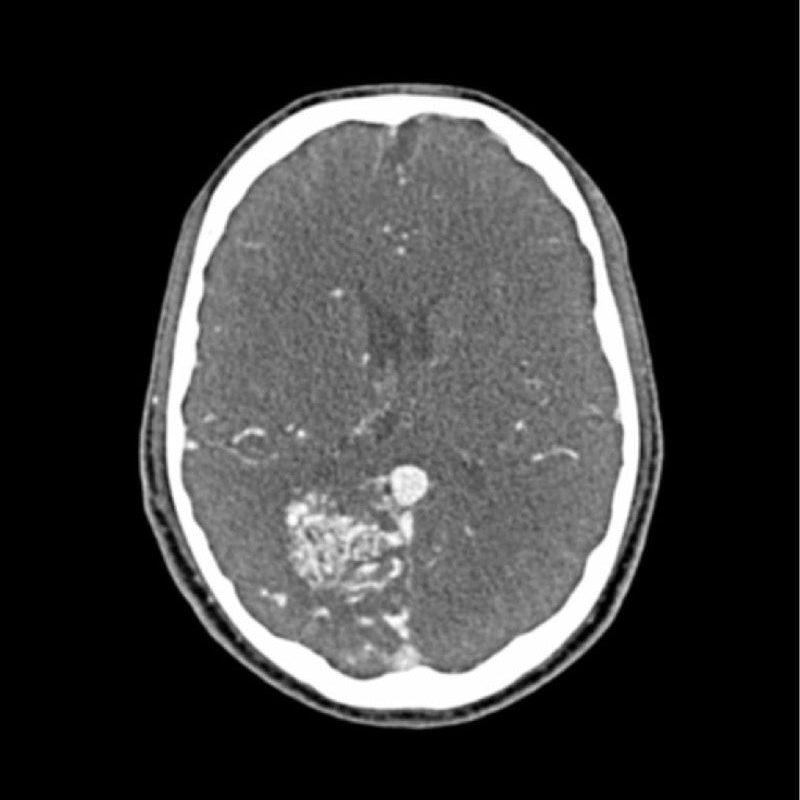

This phantom simulates a contrast medium enhanced head in arterial phase (CT angiography). It covers the vertex to the foramen magnum. The phantom has 10 low-contrast lesions in the centrum semiovale and the right hemisphere has an arteriovenous malformation.

- Arteriovenous malformation of the right hemisphere.

- 5 rod-shaped lesions on each side in the centrum semiovale at the periventricular and supraventricular level.

Lesion diameter: 10 mm

Lesion height: 10.5 mm

Lesion contrast: Approx. -60 to -20 and 20 to 60 HU at 120 kVp